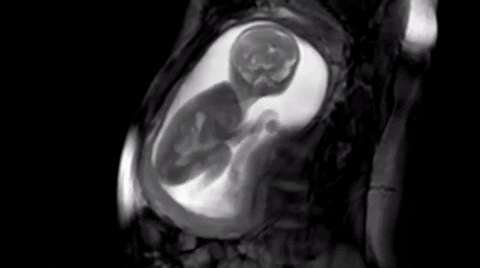

La poesía kósmica del embarazo

El kosmos y su física nos habla.

La química de la biología también.

La física nos habla del giro para manifestar.

La química nos habla de la relación para emocionar.